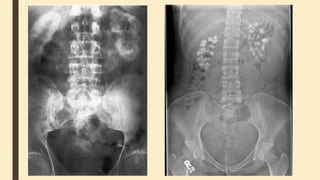

Intravenous urography

- Native abdominal imaging in order to check 1) readiness of

the patient 2) calcifications in the kidney 3) pathology of

tissues around the kidney (gas in the large intestine, spine).

- Stages:

5-7 min – renal calyces

10-15 min – urether

25-30 min – bladder

45-60 min - if the obstruction is severe and the

ureter is insufficiently opacified, perform delayed full-length

radiographs